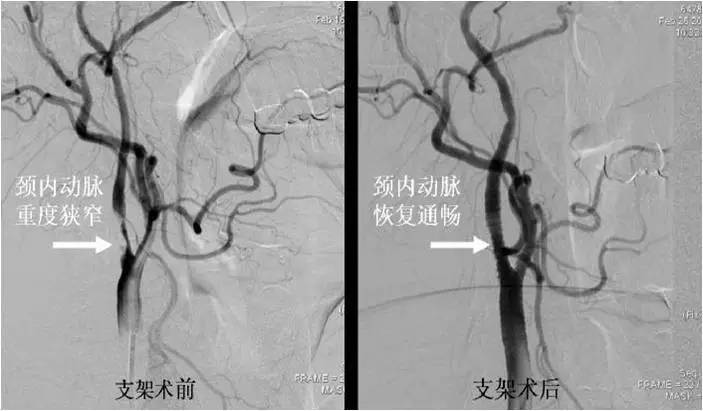

(三)颅内外动脉血管成形术

模式图

病例1:颈内动脉起始段狭窄

》男性,65岁,因发作性右侧肢体活动不灵7天入院。发作时不能行走及持物,言语表达困难,持续约10分钟左右,自行完全恢复正常,7天来共发作3次,每次发作症状基本相同。

》入院时查体:神经系统查体未见阳性定位体征。

病例2:大脑中动脉M1段狭窄

》男性,56岁,因反复右肢体无力,每次发作约数分钟自行缓解。经药物治疗3个月TIA仍反复发作既往有高血压病史10年,糖尿病病史8年。

》自带CT提示:多发腔隙性脑梗死。入院诊断:TIA,高血压病,糖尿病。行全脑血管造影,发现左大脑中动脉M1段狭窄,狭窄处植入了支架。